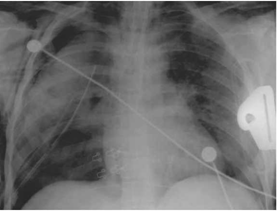

התמונה הרנטגנית מופיעה רק 12–24 שעות לאחר החבלה. בחלק מהחולים בצילום חזה ניתן לראות עכירות מוקדית המתפשטת עד קבלת "ריאה לבנה" (White lung) (תצלום 16.16). יש לעקוב אחר חולים אלה. המטומה ריאתית ניתן לראות בצילום חזה כממצא עכור בעל גבולות לא חדים, אשר הופך במשך מספר ימים עד שבועיים לעכירות מוגדרת, לפעמים תוך יצירת כיסית אשר נרפאת ללא טיפול מיוחד.